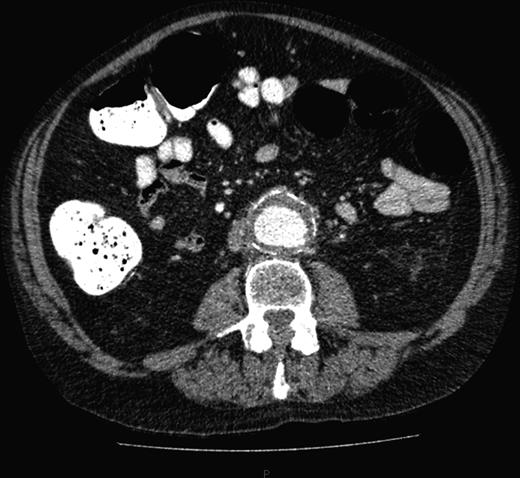

A computed tomography (CT) of the abdomen and pelvis was performed. This showed a grossly distended urinary bladder and compression of the sigmoid colon against the sacral promontory causing bowel obstruction (Figs 1 and 2, respectively) as well as a 4.9 cm abdominal aortic aneurysm without any signs of a rupture (Fig. 3). The plan was to consult our vascular colleagues regarding management of the AAA once the obstruction had settled.

Abdominal aortic aneurysm with some wall standing thrombus but without any signs of rupture.